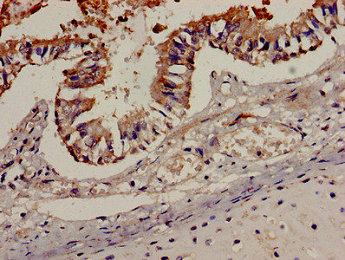

Immunohistochemistry analysis of human lung tissue using CSB-PA004846LA01HU at dilution of 1:100